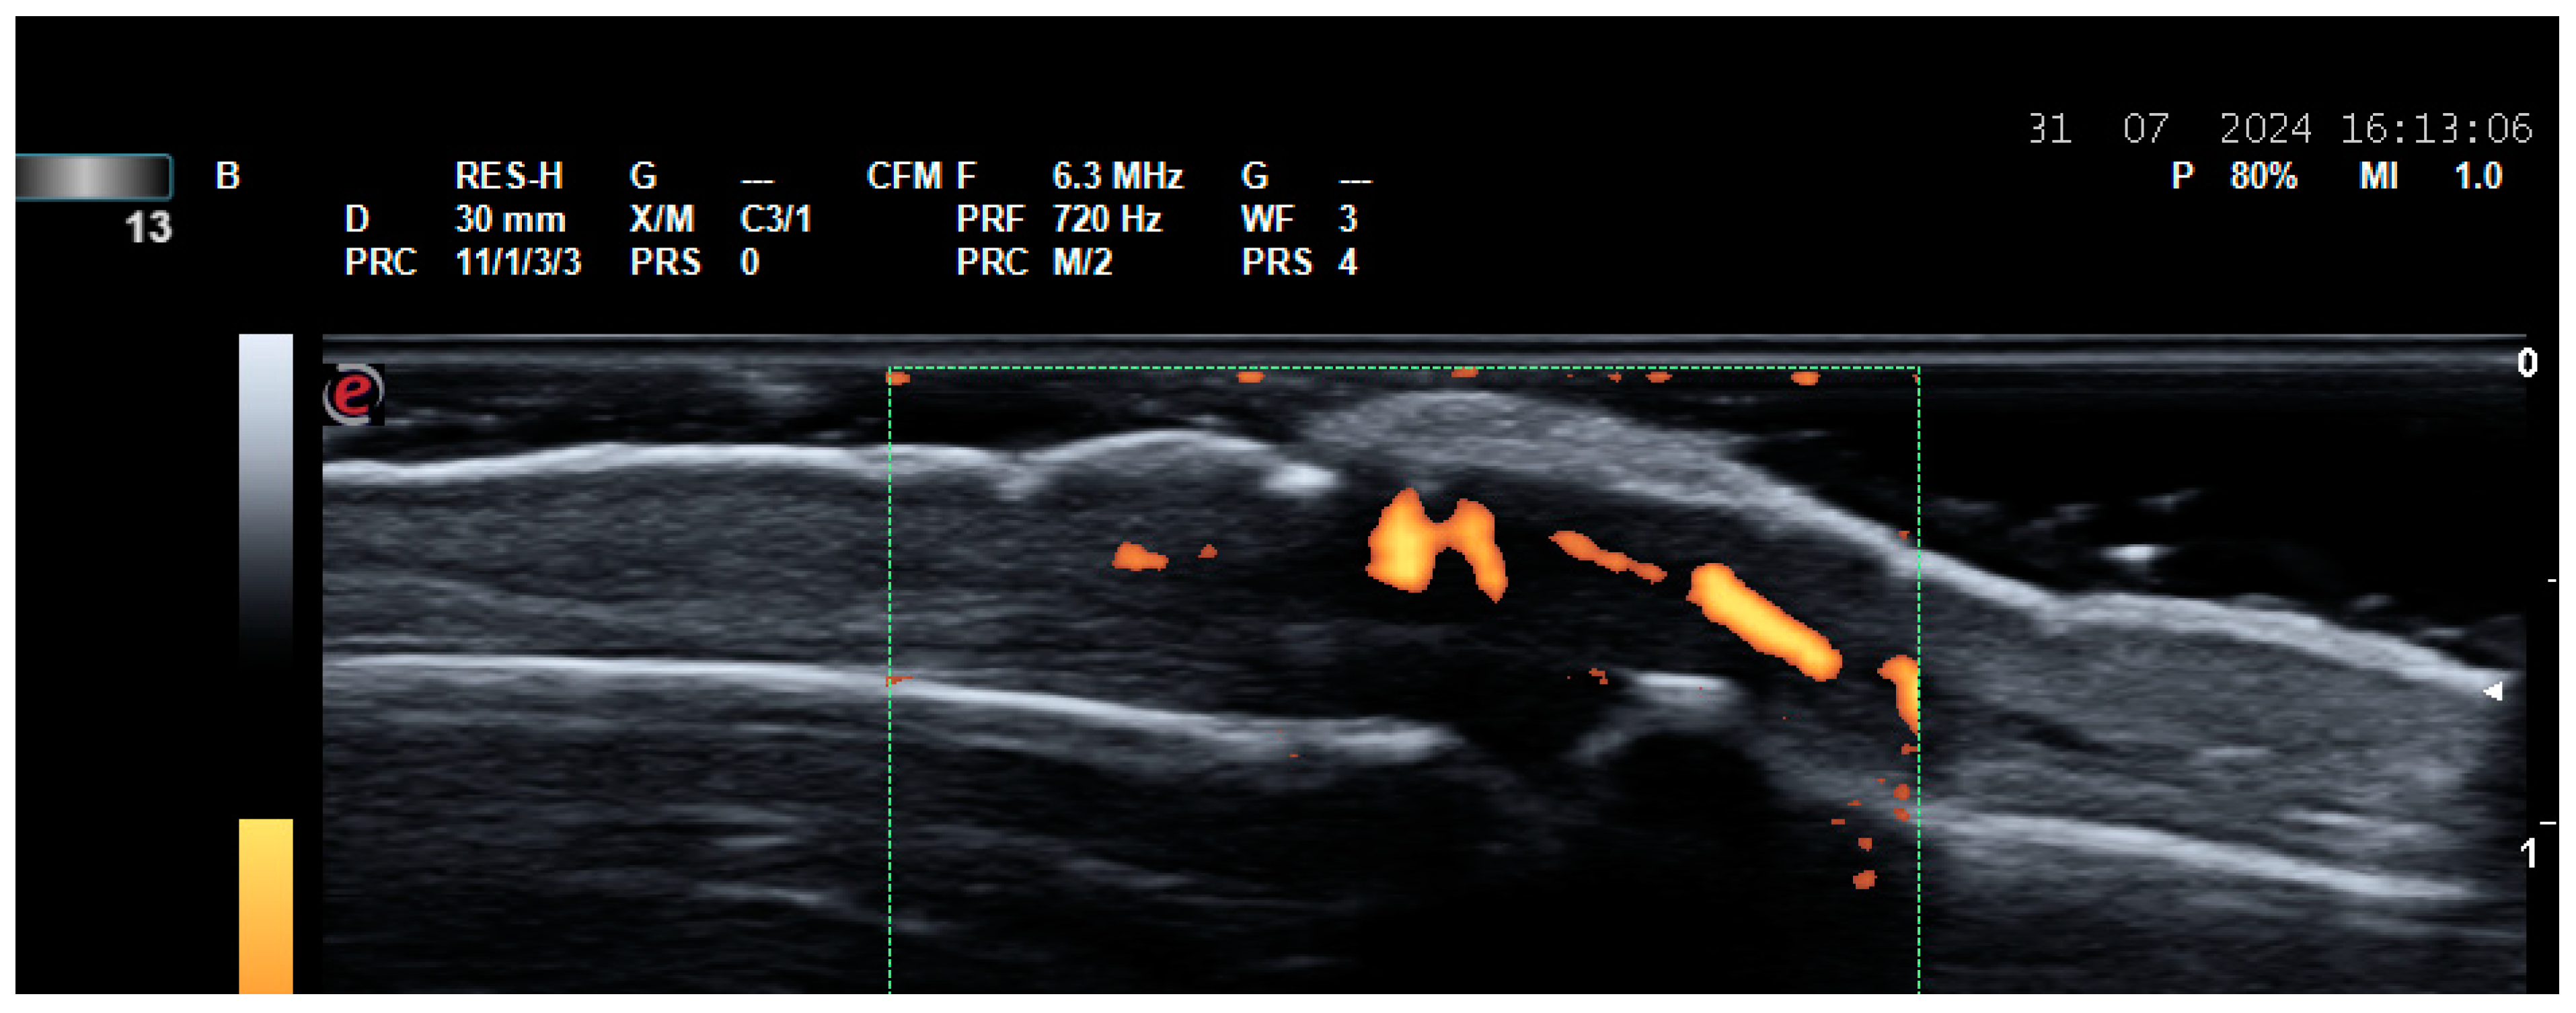

2.2. US for Assessment of Disease Activity and Monitoring Response to Therapy

- Agache, M.; Popescu, C.C.; Enache, L.; Mogoșan, C.; Filippucci, E.; Codreanu, C. Additional Value of Ultrasound in Patients with Psoriatic Arthritis within Treatment Target. J. Clin. Med. 2024, 13, 4567. [Google Scholar] [CrossRef] [PubMed] [PubMed Central]